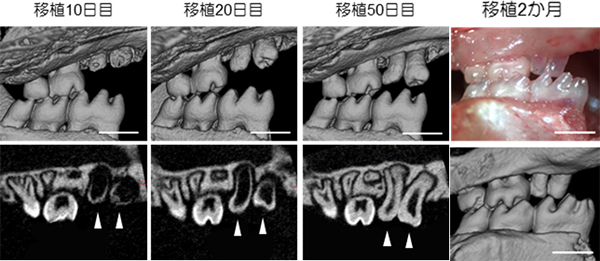

歯の再生では、分割歯胚が天然歯胚と同等の組織構造を持つだけでなく、口腔内に移植したときに、レシピエント(移植を受ける個体)の顎骨と正常に生着し、さらに周囲組織と連携し機能することが重要です。そこで、マウスの口腔内に分割歯胚を移植し、歯の発生過程をマイクロCTで観察しました(図7)。その結果、移植約2か月後には反対側の歯と咬合し、機能していることが示されました。

図7 分割歯胚の口腔内移植後の経過像

分割歯胚をマウスの口腔内に移植しマイクロCTにて萌出過程を観察した。移植約2か月後には反対側の歯と咬合していることが認められた。※スケールバー:50μm。